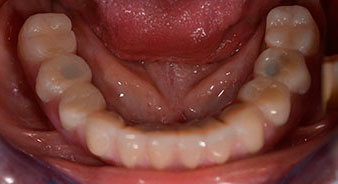

La paziente, 64 anni, presenta una dentatura residua di denti 38, 33 e 43 e una protesi combinata innestata nella mandibola (Fig. 1 e 2).

dentatura residua

Fig. 1

Fig. 2